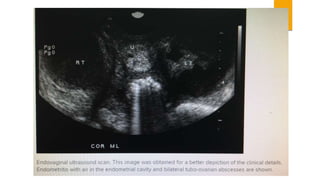

 SONOGRAPHY- Dilated and fluid-filled tubes, fluid in the pouch of

doughlas or adnexal mass are suggestive of PID.